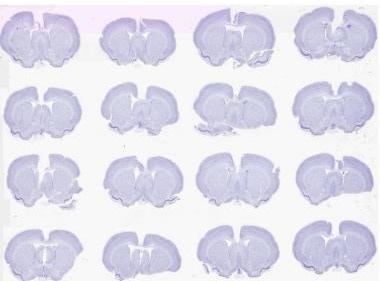

Figure 2. Brightfield scan of 16 Nissil stained rodent brains on a 2” x 3” slide at 0.5 μm. Image credit: Huron Digital Pathology.

- A proprietary laser-scan lens and optical configuration enables a broad (5 to 10mm) field-of-view and therefore the imaging of more rodent brain sections per unit area (up to 48 square inches area).